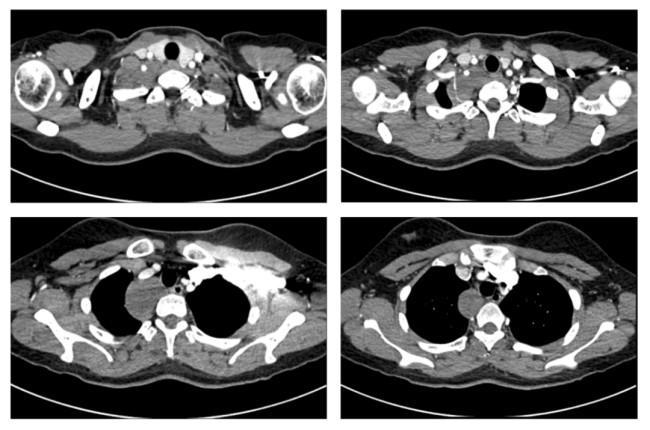

患者是一名來自新疆的19歲女生,在校期間一次常規體檢中偶然發現后縱隔腫物。因腫物位置特殊,患者及家屬在當地多家醫院輾轉求醫,最終慕名到省立醫院劉相燕主任處就診。入院后,患者完善了胸部CT平掃+增強檢查,影像顯示,腫物上緣至甲狀腺水平,向下沿氣管及食管走行,累及長度近6厘米,與右鎖骨下動脈關系密切,幾乎完全包繞椎動脈。此外,腫瘤已累及交感神經,緊鄰臂叢神經,術中稍有不慎極易損傷重要的血管、神經,導致嚴重的并發癥。這極大增加了手術難度與風險,對手術團隊提出了挑戰。針對患者復雜的病情,劉相燕主任帶領團隊制定了詳盡的手術方案,就手術切口選擇、術中突發狀況應急處理以及術后生命體征與神經功能監測等環節均進行了充分討論與周密準備。

患者術前胸部增強CT影像資料